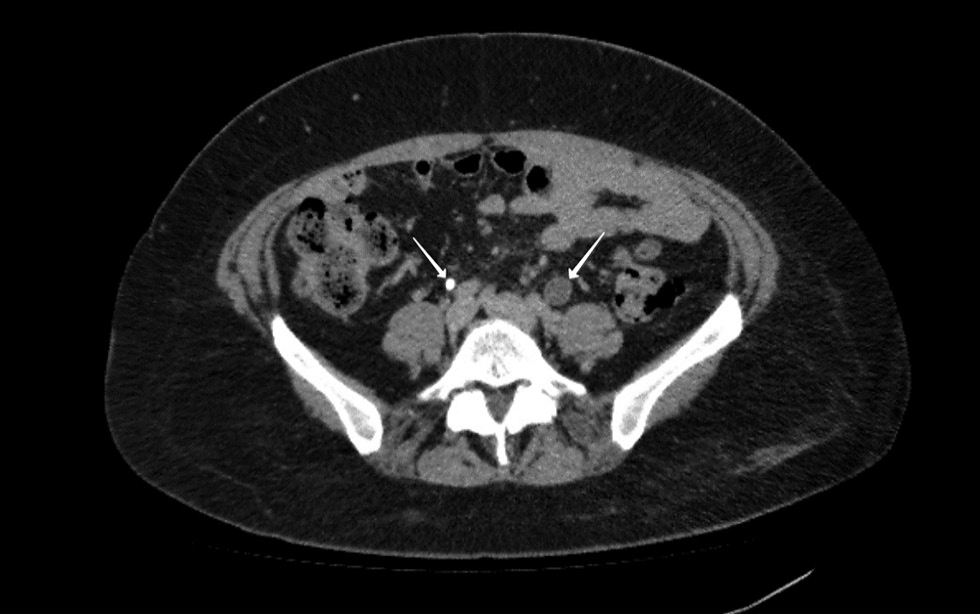

Рис. 2. Компьютерная томография органов брюшной полости. Стрелкой указан свободный газ в просвете мочевого пузыря

Fig. 2. Computed tomography of the abdomen. The arrow indicates free gas in the bladder cavity

По данным контрольной КТ от 17.03.2022: в левой половине малого таза над мочевым пузырем определяется конгломерат петель кишки, заполненный содержимым, не отделимый от стенки мочевого пузыря, утолщенной и накапливающей рентгенконтрастный препарат. В просвете мочевого пузыря обнаружен воздух (рис. 2.). Отмечен отек внутритазовой клетчатки, расширение тазовых сплетений слева. Дистальный отдел левого мочеточника теряется в инфильтрате, присутствует умеренная левосторонняя пиелоуретероэктазия (рис. 3, 4).